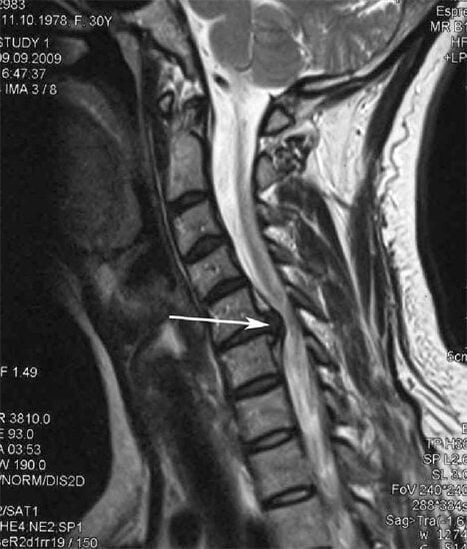

Սկզբնական փուլերում օստեոխոնդրոզը հայտնաբերվում է MRI-ի միջոցով. Հետագայում պաթոլոգիան կարող է ախտորոշվել ռադիոգրաֆիայի միջոցով: Արգանդի վզիկի ողնաշարի ռադիոգրաֆիաներում նկատելի են դառնում ողնաշարերի միջև հեռավորության նվազում, ֆասետային հոդերի պաթոլոգիական փոփոխություններ և օստեոֆիտոզ:

Շատերը բողոքում են, որ չեն կարողանում պարանոցը շրջել ծանր ցավից, որն առաջանում է հանկարծակի ծանր բան բարձրացնելուց հետո։ Այս երեւույթը վկայում է սկավառակի ճողվածքի առաջացման մասին: Մեջքի, պարանոցի և վերին վերջույթի ցավերի պատճառը ողնուղեղից դուրս եկող նյարդային արմատներից մեկի կծկումն է։